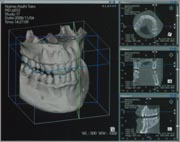

![]() Computed Tomographyの略で、通常はX線を用いて生体の断層像を得るX線CTをさします。 「物体の内部構造は、その物体を複数の方向から投影して得られた情報から再構成することができる」という基本原理に基づいている。 実際には生体のある断面に多方向から幅の狭いX線ビームを曝射(ばくしゃ)し、 透過したX線を検出してその断面内でのX線の吸収の度合いの空間分布をコンピュータで計算し画像化している。 人体の最初のCT画像は1972年にイギリス放射線学会でハウンズフィールドGodfrey N. Hounsfield(1979年ノーベル医学生理学賞受賞)により、 computerized axial transverse scanningという名称で発表された。それ以来、X線によるスキャン方法と検出系さらに画像再構成技術の開発進歩により、 空間分解能と濃度分解能に加え時間分解能にも優れた断層撮影法として、CTは全身の画像診断に革命的な進歩をもたらしています。 |

![]() インプラントの治療には正確な距離計測が必要となります。 CT撮影により正確な距離を計測します。 |

![]() 三次元構築し、全体を把握します。 |

![]() 個々の部位の計測を行い、各部位を精確に診断していきます。 |

![]() 最先端技術であるインプラントおよび歯科矯正治療を行うためにCTは必要不可欠です。 |